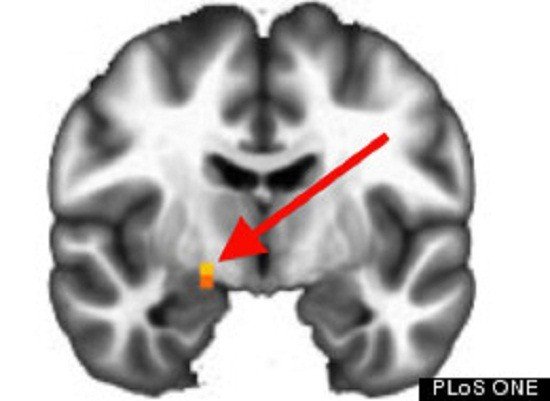

共和党大脑右侧的杏仁核表现出明显的活跃性。

大多数民主党拥有自由的价值观,而大多数共和党有着保守的价值观。通过对比发现民主党和共和党参与者在两个大脑区域存在差异:右侧杏仁核和左后侧的脑岛。当做出风险决定的时候,共和党在右侧杏仁核表现的比民主党更加活跃。这一大脑区域对于处理恐惧、风险和报酬是非常重要的。民主党在左后侧的脑岛表现的更加活跃,这一大脑区域负责情感处理,特别是身体内脏的情绪提示。